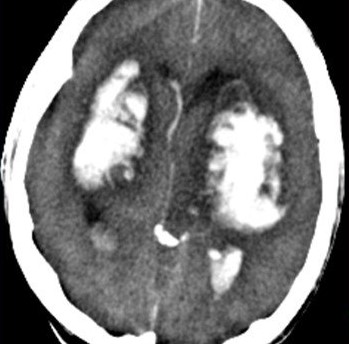

Портальная энцефалопатия